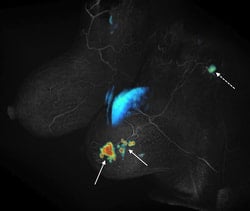

Spatial and temporal resolution are competing requirements in dynamic MRI, often requiring compromises. We are developing methods based on view sharing, compressed sensing and combinations of the two along with novel acquisition schemes to accelerate dynamic contrast enhanced imaging. The main applications are in cancer imaging (breast, prostate, liver) as well as quantification of renal function. One such method called Differential Subsampling with Cartesian Ordering or DISCO is now a product on GE MRI scanners. The picture on the left shows initial slope of contrast enhancement wash-in overlaid on a DISCO post contrast image obtained from a patient with invasive ductal carcinoma (solid arrows) with a likely metastatic axillary node (dotted arrow).

Spatial and temporal resolution are competing requirements in dynamic MRI, often requiring compromises. We are developing methods based on view sharing, compressed sensing and combinations of the two along with novel acquisition schemes to accelerate dynamic contrast enhanced imaging. The main applications are in cancer imaging (breast, prostate, liver) as well as quantification of renal function. One such method called Differential Subsampling with Cartesian Ordering or DISCO is now a product on GE MRI scanners. The picture on the left shows initial slope of contrast enhancement wash-in overlaid on a DISCO post contrast image obtained from a patient with invasive ductal carcinoma (solid arrows) with a likely metastatic axillary node (dotted arrow).